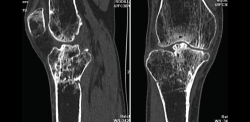

1. Fracturas

Es esencialmente útil en la valoración de los trazos de fractura, de su extensión, del escalón intraarticular y el desplazamiento. También es importante en la planificación del tratamiento de las fracturas intraarticulares complejas.

Los nuevos equipos, con múltiples detectores, permiten realizar cortes finos (submilimétricos) y reconstrucciones en cualquier plano del espacio o tridimensionales (3D) de gran calidad, que facilitan la valoración de estas lesiones(7).

1.2. Tibia (Figura 20)

Figura 20. Corte de reconstrucción coronal de tomografía axial computarizada de rodilla: fractura de ambas mesetas tibiales.